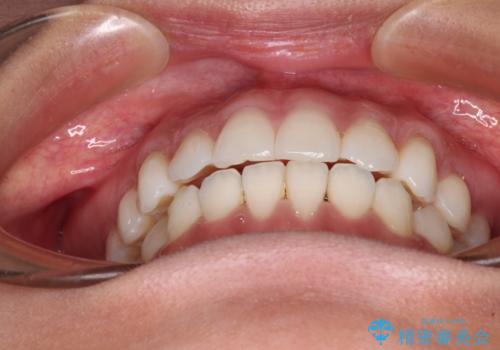

【モニター】インビザラインで口を閉じやすく

- 前に出ている上顎前歯が気になるとのことで来院された患者様です。

インビザラインを用い、IPR(歯と歯の間を削る)と歯列全体を後方に移動させることで、可能な限り前歯の突出感を改善することとしました。

元々の歯列も整っており、横顔の印象の出っ歯ではなかったため、仕上がりに満足できない可能性があると心配しておりましたが、口が閉じやすくなり、患者様には大変満足していただきました。